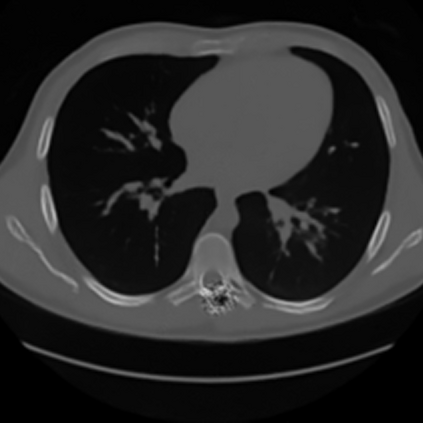

Sparse-view computed tomography (CT) -- using a small number of projections for tomographic reconstruction -- enables much lower radiation dose to patients and accelerated data acquisition. The reconstructed images, however, suffer from strong artifacts, greatly limiting their diagnostic value. Current trends for sparse-view CT turn to the raw data for better information recovery. The resultant dual-domain methods, nonetheless, suffer from secondary artifacts, especially in ultra-sparse view scenarios, and their generalization to other scanners/protocols is greatly limited. A crucial question arises: have the image post-processing methods reached the limit? Our answer is not yet. In this paper, we stick to image post-processing methods due to great flexibility and propose global representation (GloRe) distillation framework for sparse-view CT, termed GloReDi. First, we propose to learn GloRe with Fourier convolution, so each element in GloRe has an image-wide receptive field. Second, unlike methods that only use the full-view images for supervision, we propose to distill GloRe from intermediate-view reconstructed images that are readily available but not explored in previous literature. The success of GloRe distillation is attributed to two key components: representation directional distillation to align the GloRe directions, and band-pass-specific contrastive distillation to gain clinically important details. Extensive experiments demonstrate the superiority of the proposed GloReDi over the state-of-the-art methods, including dual-domain ones. The source code is available at https://github.com/longzilicart/GloReDi.